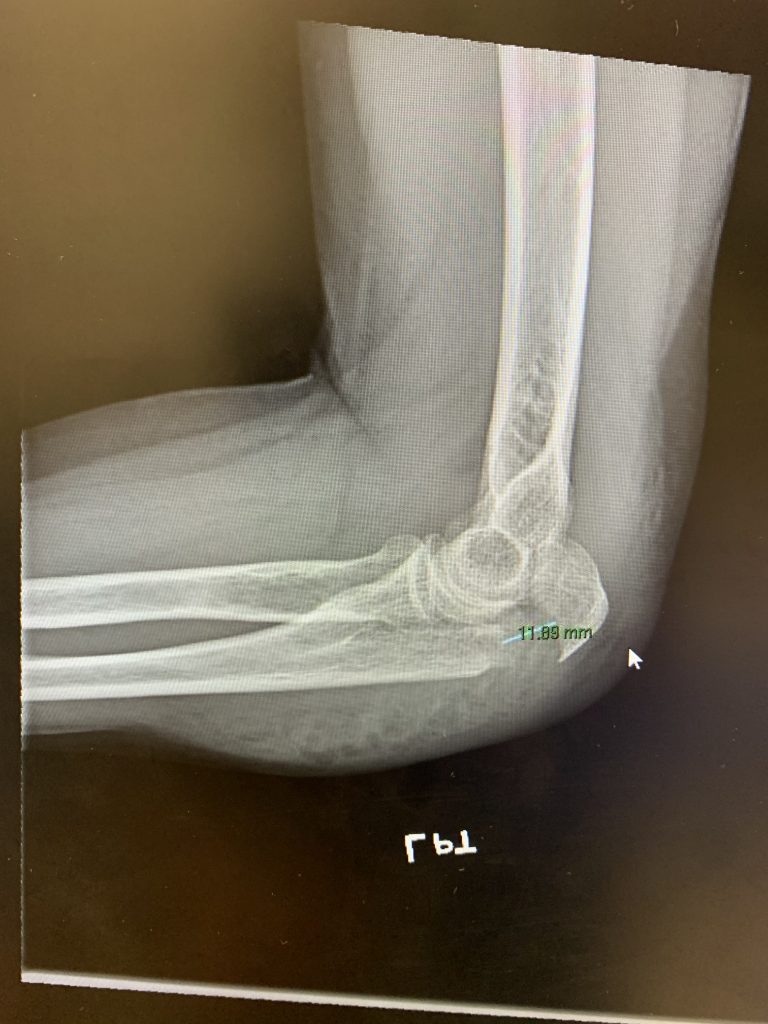

Arm and Elbow Fractures